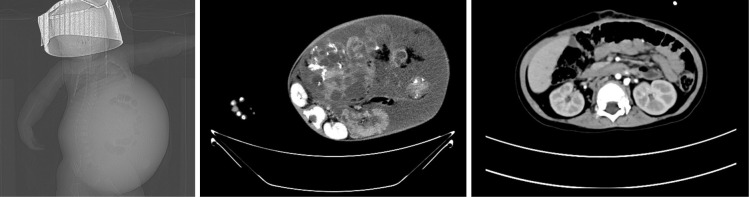

Case description: The patient was a male infant, presented with a palpable mass in the upper abdomen at 4 months of age. Initial ultrasound and elevated serum alpha-fetoprotein (AFP) levels suggested a retroperitoneal teratoma. After surgery, the diagnosis was confirmed as an IMT [World Health Organization (WHO) grade III]. Despite initial chemotherapy with BEP (bleomycin, etoposide, and cisplatin) and TIC (nab-paclitaxel, ifosfamide, and carboplatin) regimens, the tumor continued to grow, and the patient experienced GTS. A second surgery was performed, and the patient was subsequently treated with TCAV (nab-paclitaxel, cyclophosphamide, epirubicin and vincristine) and TIC chemotherapy, leading to normalization of AFP levels and no evidence of disease over a 4-year follow-up.